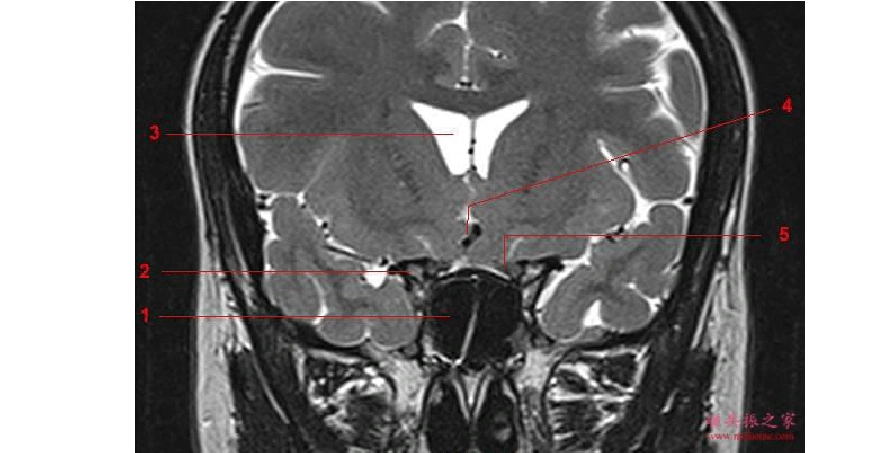

病例三,男,57,颅脑磁共振体检中发现垂体病变,高度可疑垂体瘤

(精选)鞍区垂体mri解剖

垂体病变